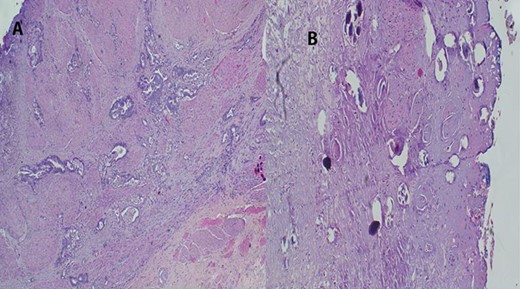

The report revealed a segment of colon with low-grade invasive adenocarcinoma (pT3NxM1) and Schistosoma eggs embedded in the tumor (Fig. 3).

(A) Histopathology of colon with adenocarcinoma associated with Schistosoma ova with poorly formed granulomatous inflammation, hematoxylin and eosin (H&E) ×20 magnification. (B) Adenocarcinoma and Schistosoma ova with dense lymphocytic infiltrates ×40 magnification.